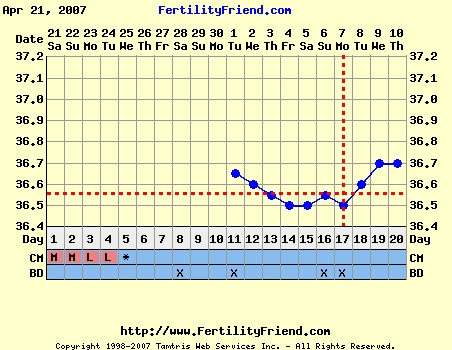

Bettike, Sztem is jelöld a fertyn ha beteg vagy, de nagyon nagyon drukkolok hogy más miatt legyél ilyan sz*rul